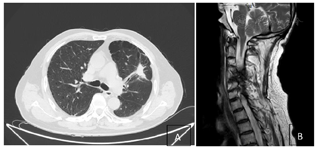

实验室检查:血细胞分析:红细胞2.93×10^12/L↓;血红蛋白103.00g/L↓;白细胞3.40×10^9/L↓;中性粒细胞绝对值1.77×10^9/L↓;肝功能:白蛋白37.50g/L↓;总蛋白58.00g/L↓;电解质(血液):钾3.44mmol/L↓;免疫功能检测提示多项指标低下。影像学检查:脑MRI、全身骨扫描、腹部彩超未见明显异常。胸部CT增强(治疗前后):2021年5月左肺上叶前段软组织密度影(4.3×2.4cm)(图1)。治疗后左肺上叶舌段肿块(大小约2.5×1.6cm),较前减小(图2)。颈椎MRI(治疗前后):2021年5月颈5椎体病理性骨折、左侧椎旁软组织肿块形成(图1)。治疗后左侧椎旁软组织肿块较前缩小(图2)。